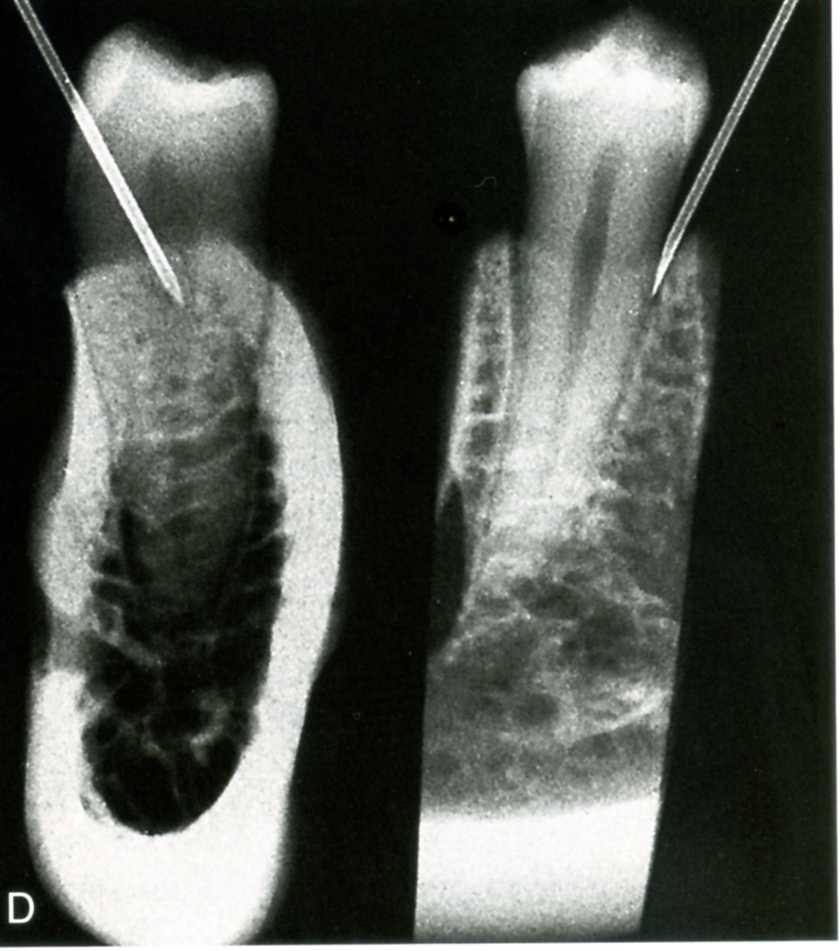

III – GÂY TÊ TRỰC TIẾP VÀO TỦY ĐỂ CHỮA TỦY (TÊ ÉP BUỒNG):

Phương pháp gây tê để chữa tủy này đưa thuốc tê trực tiếp vào tủy buồng hoặc tủy chân. Cần lưu ý rằng, phương pháp gây tê để chữa tủy răng này gây đau đớn nhiều cho bệnh nhân và có thể đẩy mô nhiễm khuẩn ra vùng quanh chóp, vị vậy chỉ áp dụng khi các phương pháp gây tê lấy tủy răng khác không mang lại hiệu quả như mong muốn

Kỹ thuật gây tê ép buồng để chữa tủy răng.

Kỹ thuật gây tê trong điều trị tủy răng này được thực hiện như sau:

Sau khi đã mở thông vào buồng tủy, lau khô buồng tủy rồi nhỏ vài giọt thuốc tê, chờ vài phút

Đưa kim vào miệng ống tủy, cần lưu ý không đưa quá sâu, sao cho kim nằm trong ống tủy phải lỏng, bơm rất chậm vài giọt thuốc tê, nếu đầu kim chặt thì cần rút ra 1 khoảng rồi mới bơm thuốc, có thể bẻ kim cong 1 góc 45 độ để dễ đưa kim vào